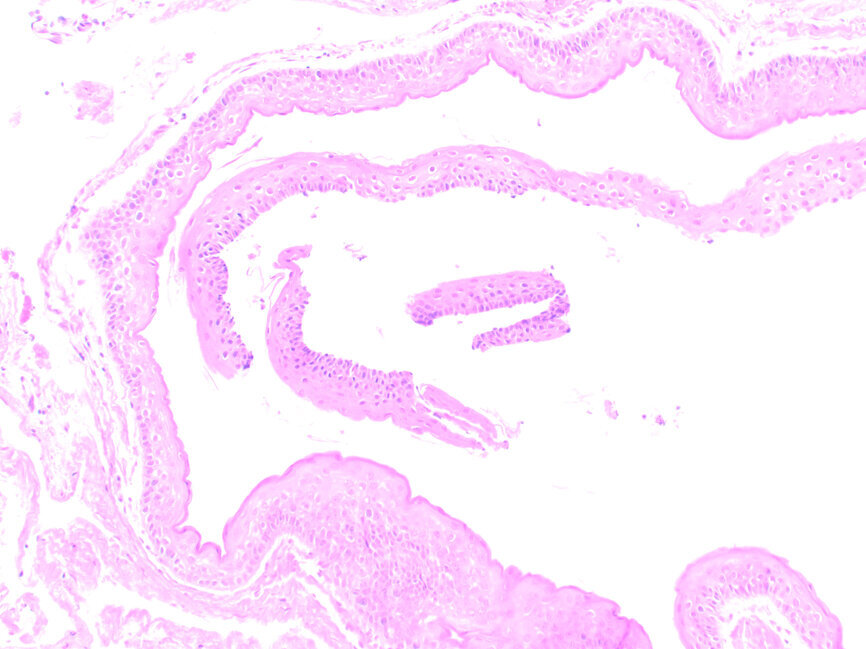

Pacjent zgłosił się na wizytę kontrolną w maju br., tj. 1,5 roku po zabiegu. Badanie kliniczne nie wykazało nieprawidłowości, widoczne była jedynie dyskretna blizna pozabiegowa (Ryc. 3). Wykonane badanie CBCT ujawniło prawidłową strukturę i ubeleczkowanie wygojonej loży po torbieli (Ryc. 4).

Ryc. 3: Stan 18 miesięcy po zabiegu.